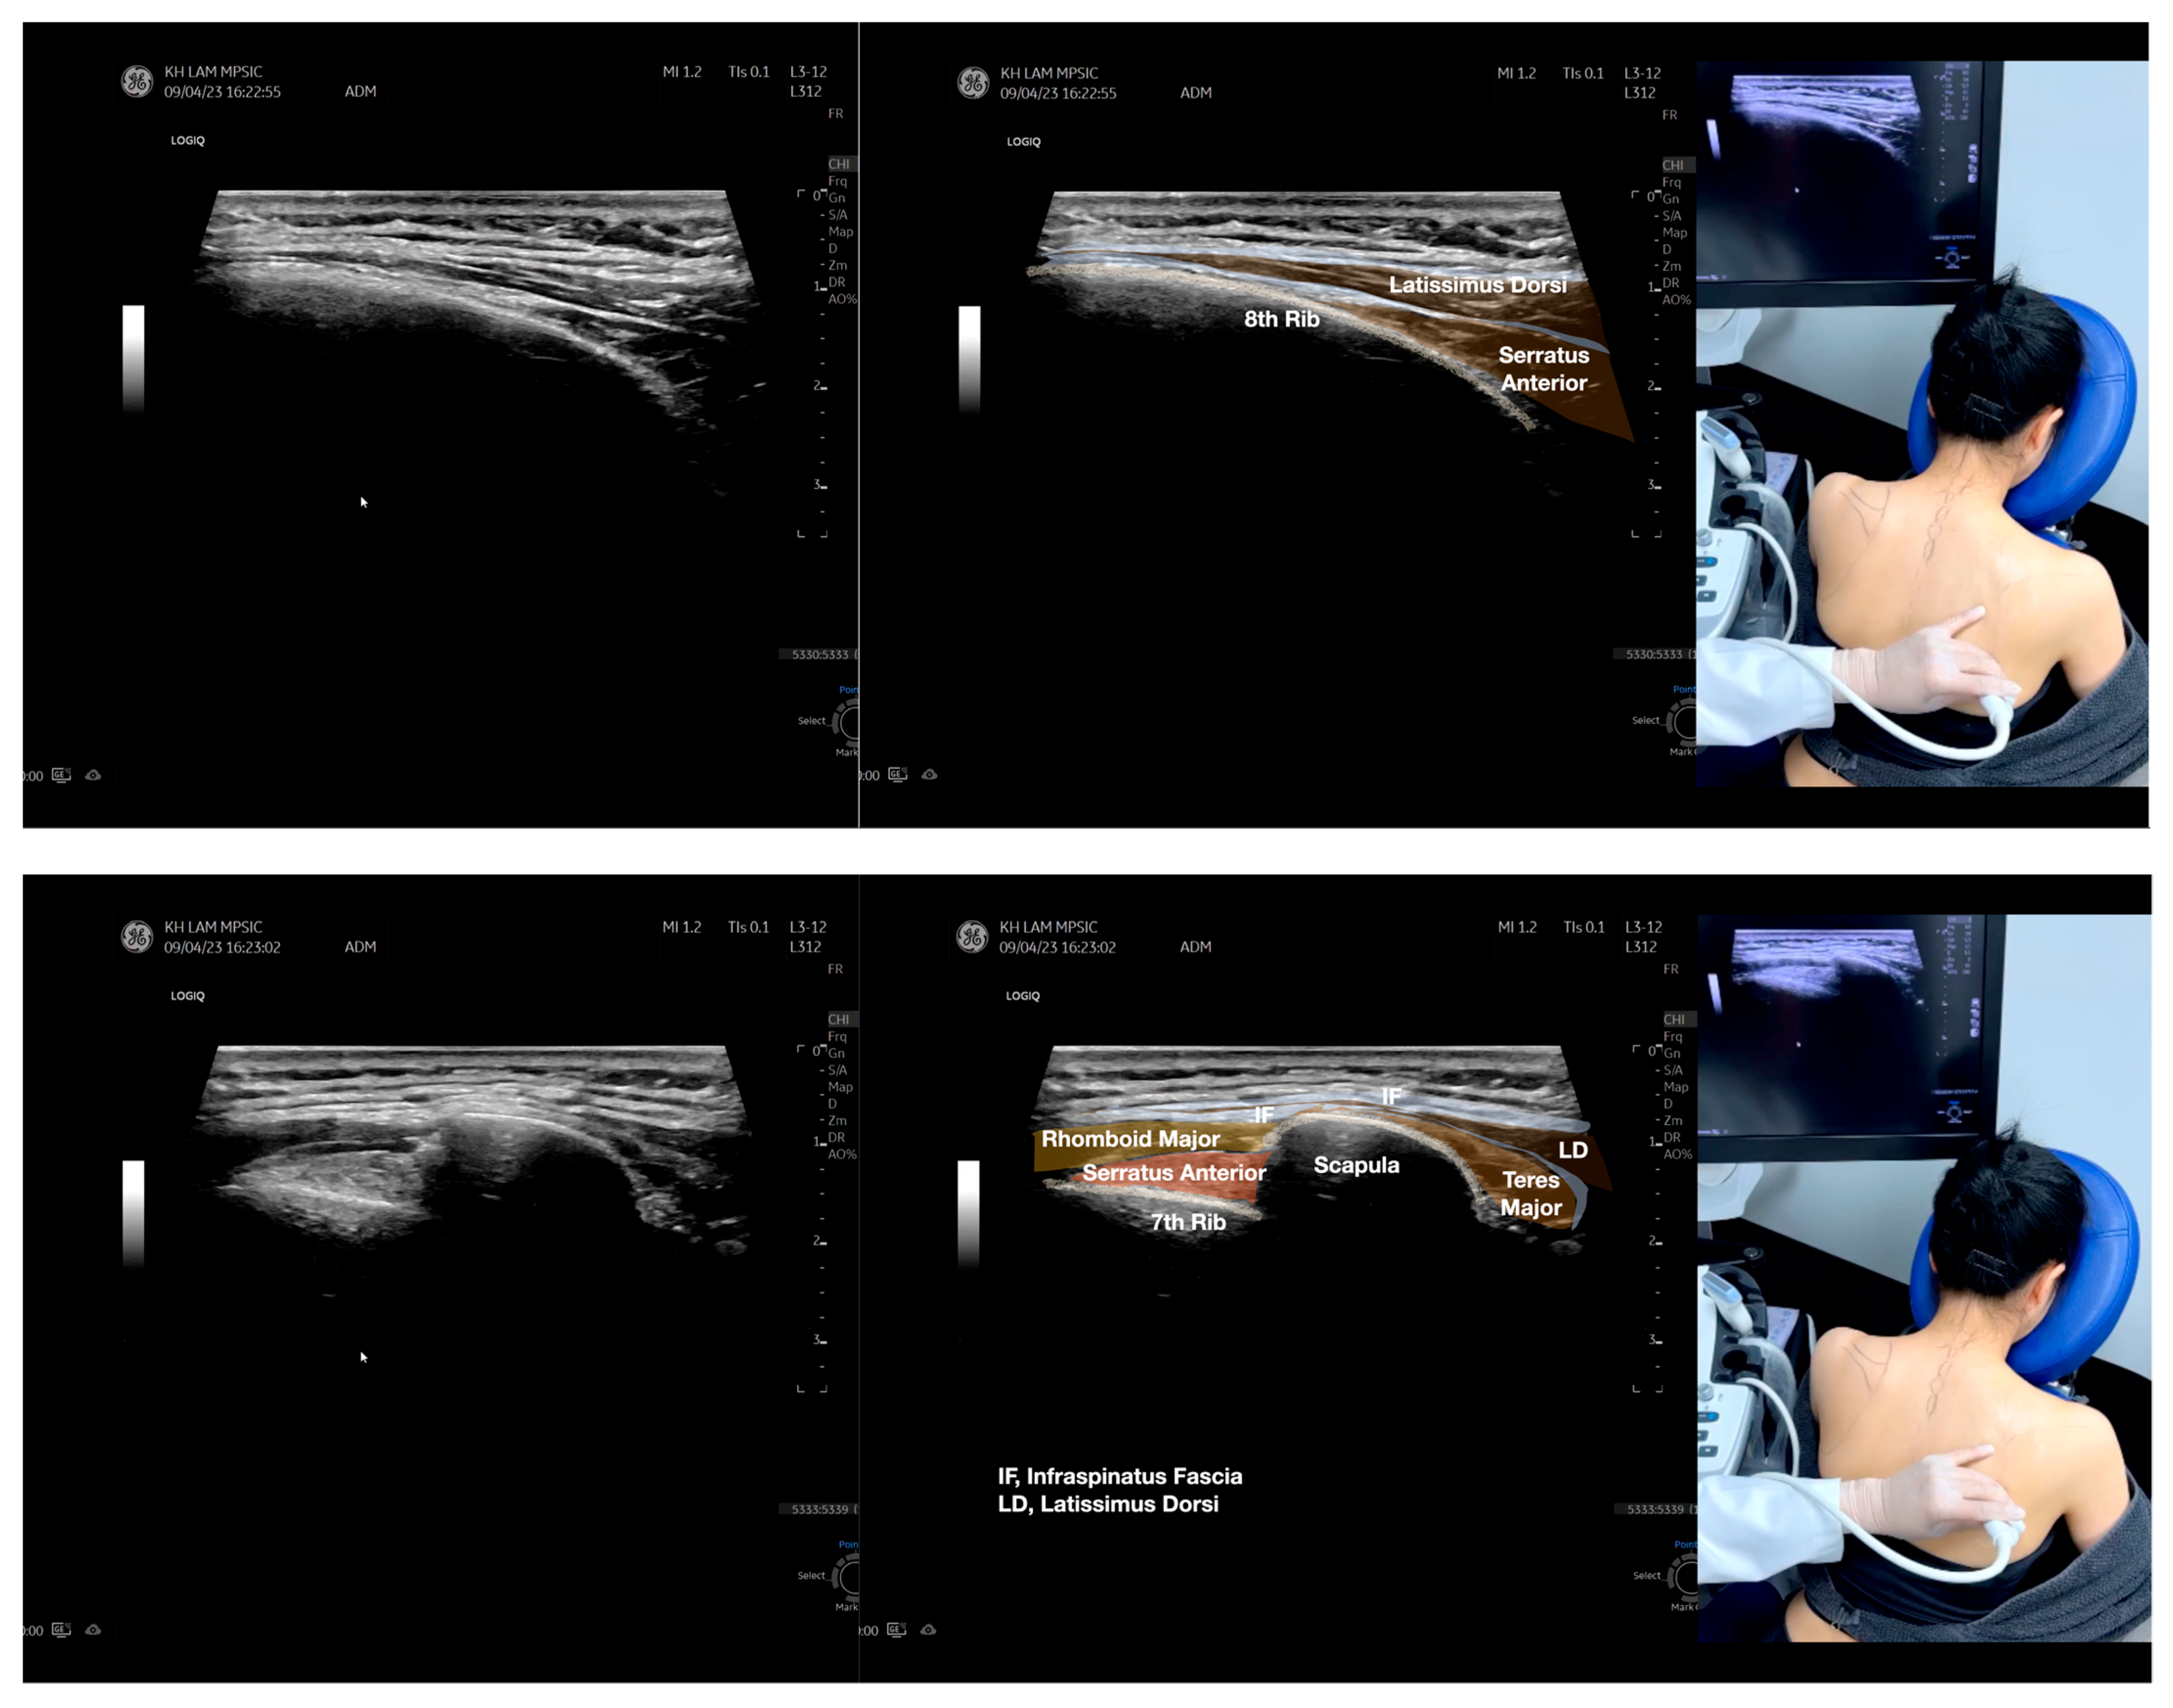

Figure 3.

Sonoanatomy of the lateral boarder of the scapular, its related muscles, and the infraspinatus fascia. Video S7 has demonstrated the step-by-step scanning techniques of these structures shown in this figure. Available online: https://www.dropbox.com/s/891m19vvw6bak34/Figure%203.docx?dl=0 (accessed on 1 January 2023).